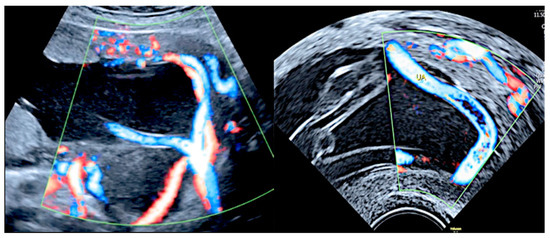

3.1.3. Bilobed Placenta and Succenturiate Lobe

3.2.2. Vasa Praevia

3.2.3. Velamentous Umbilical Cord Insertion